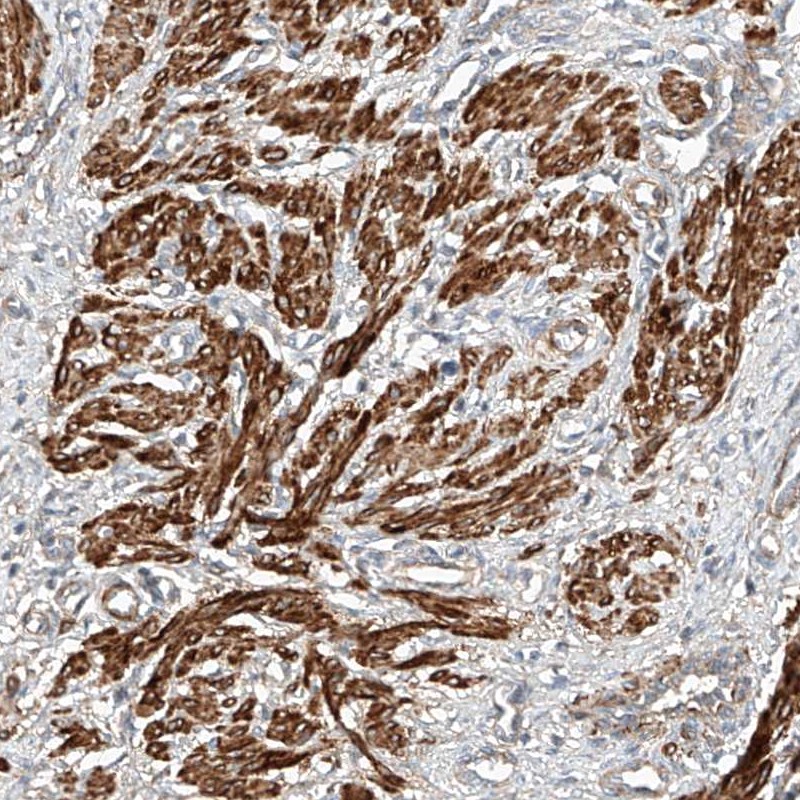

Immunohistochemical staining of human smooth muscle shows strong cytoplasmic positivity in smooth muscle cells.